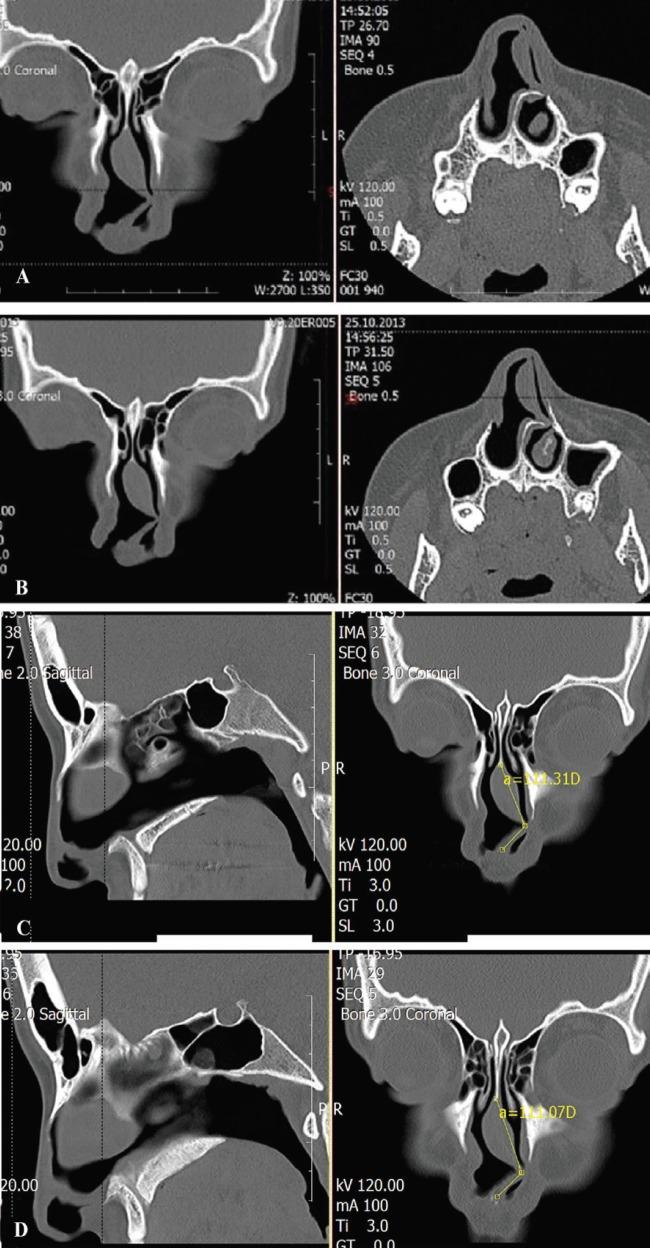

Nasal Septum and External Nasal Deformity Similarities in Monozygotic Twins and Paranasal Computed Tomography Analysis.

Since identical twins occur as a result of the division of one egg, they have the same genetic structure. Therefore, their phenotypes and sex are also always the same. However, due to the effect of environmental factors, some of the characteristics of twins living in different regions appear to develop differently. In our case of 17-year-old maternal twins, we emphasized that nasal pathologies carried a genetic background in terms of their similarity in septum deviation and external nasal deformity, which were determined to have occurred without a history of trauma. The article has also been presented at 10 Turkish Rhinology Congress, 22-25 May, 2014 Antalya, Turkey.

由于同卵双胞胎是由一个卵子分裂而成,他们具有相同的基因结构。因此,他们的表型和性别也总是相同的。然而,由于环境因素的影响,生活在不同地区的双胞胎的某些特征似乎发展得有所不同。在我们这个17岁的同母异父双胞胎案例中,我们强调,鼻中隔偏曲和鼻外形畸形方面的相似性表明鼻部病变具有遗传背景,且这些病变是在没有外伤史的情况下出现的。本文还在2014年5月22日至25日于土耳其安塔利亚举行的第10届土耳其鼻科学大会上发表。